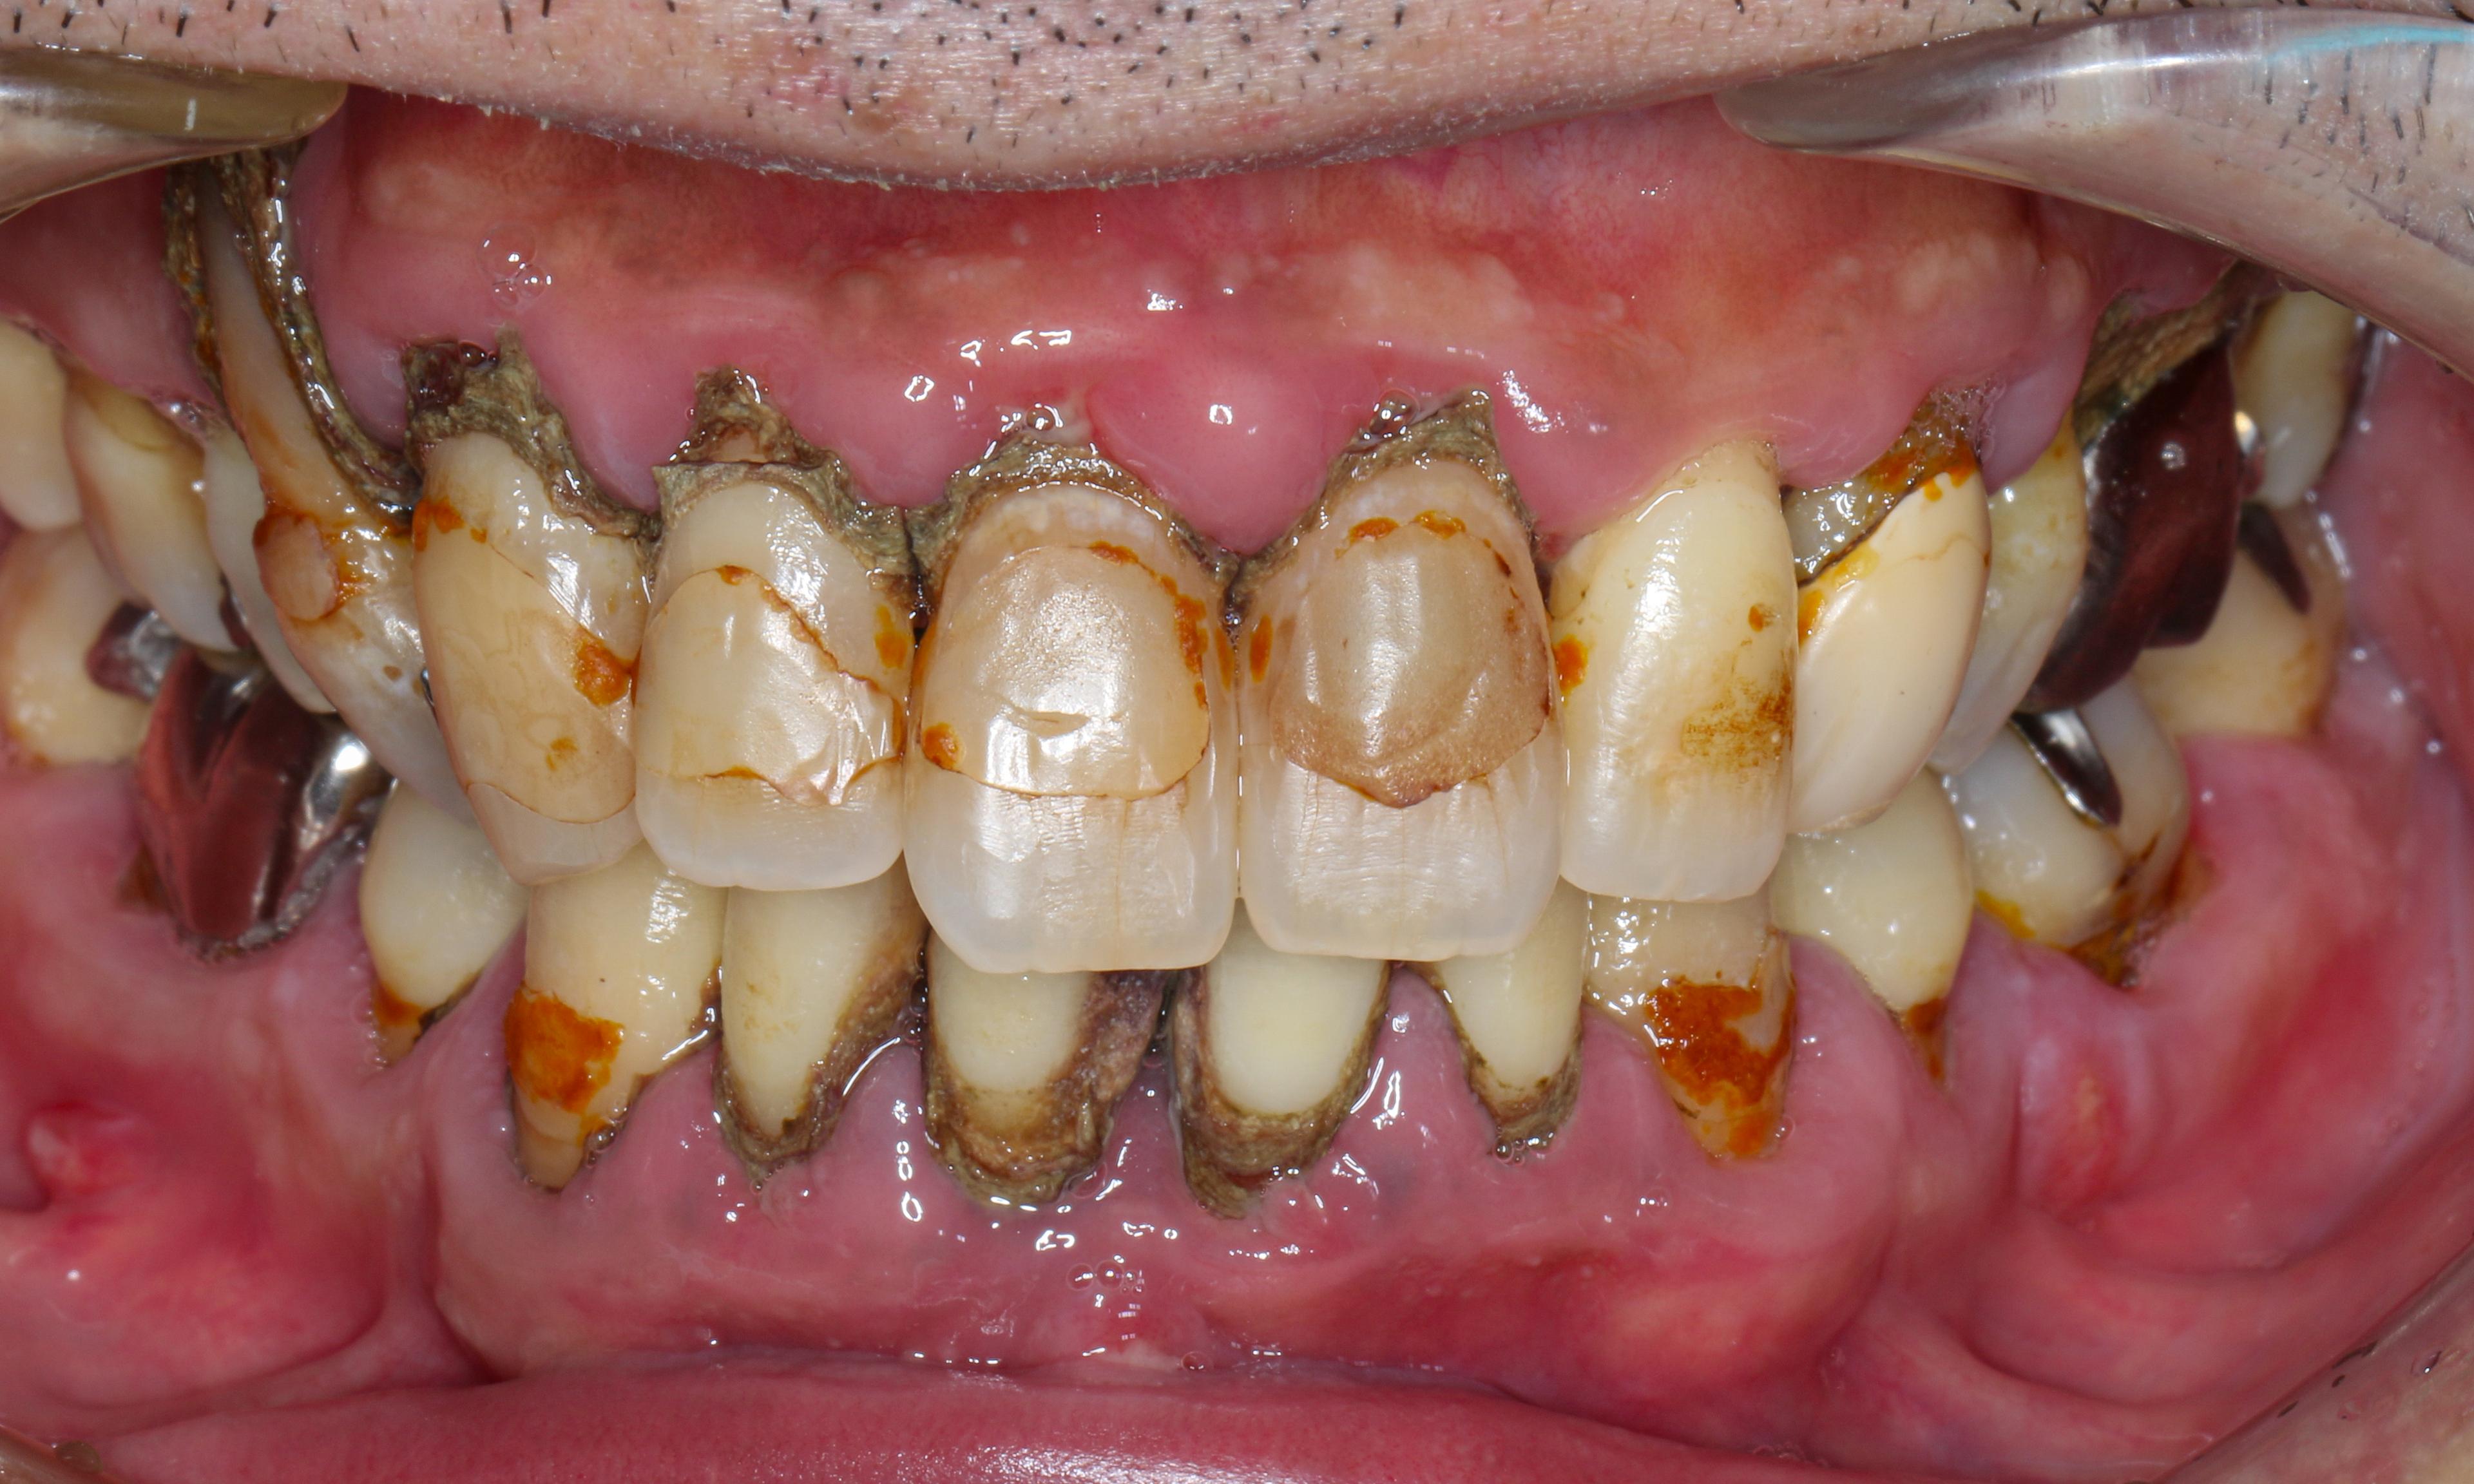

歯周ポケット測定不能。教科書的に100%抜歯の重度慢性歯周炎。原因除去療法とマイクロスコープを使った低侵襲の歯周組織再生療法により、抜歯を回避して回復した症例です。

指数病の治療をしたいということでご来院された40代の男性です。写真で分かるとおり歯石がびっしりと着いており歯周炎により歯茎の腫れも相当ある状態でした。

- 広汎型慢性歯周炎 ステージ3 グレードC

と診断をいたしました。